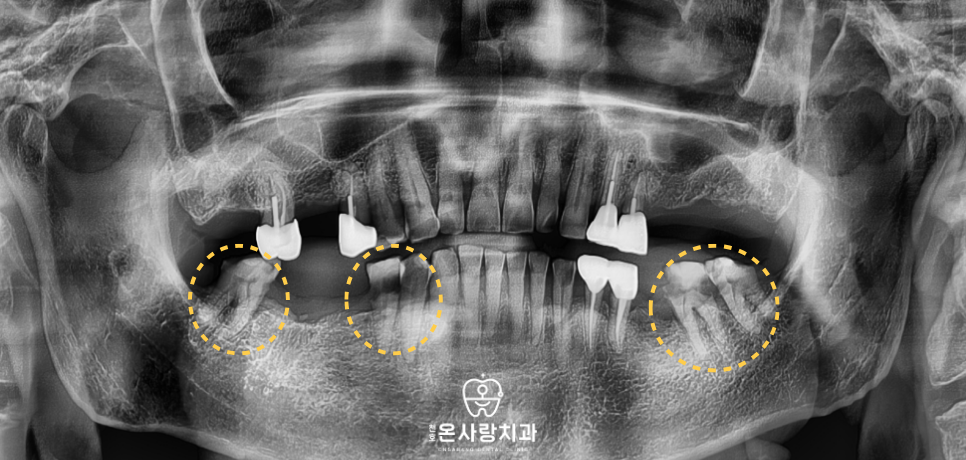

정밀 진단을 통해 하악 상태를 면밀히 분석한 결과

남아 있는 치아들의 손상 정도가 심해

정상적인 저작이 불가능하다는 판단을 내렸습니다.

치료 과정에서는 환자분이 느끼시는

하악의 통증 원인을 발치를 통해 먼저 제거하고

잇몸의 상태를 안정시키는 데 주력하였습니다.

이후 상악에 사용 중인 부분의치와의

높낮이를 맞추는 정교한 과정을 거쳤습니다.